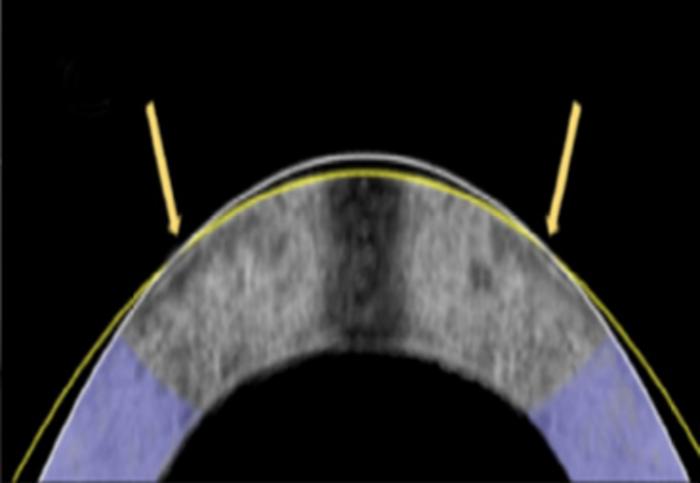

The electromechanical reshaping technique successfully flattened this rabbit cornea, shown in a cross section, from its original shape (white line) to a corrected one (yellow line).

Credit: Daniel Kim and Mimi Chen